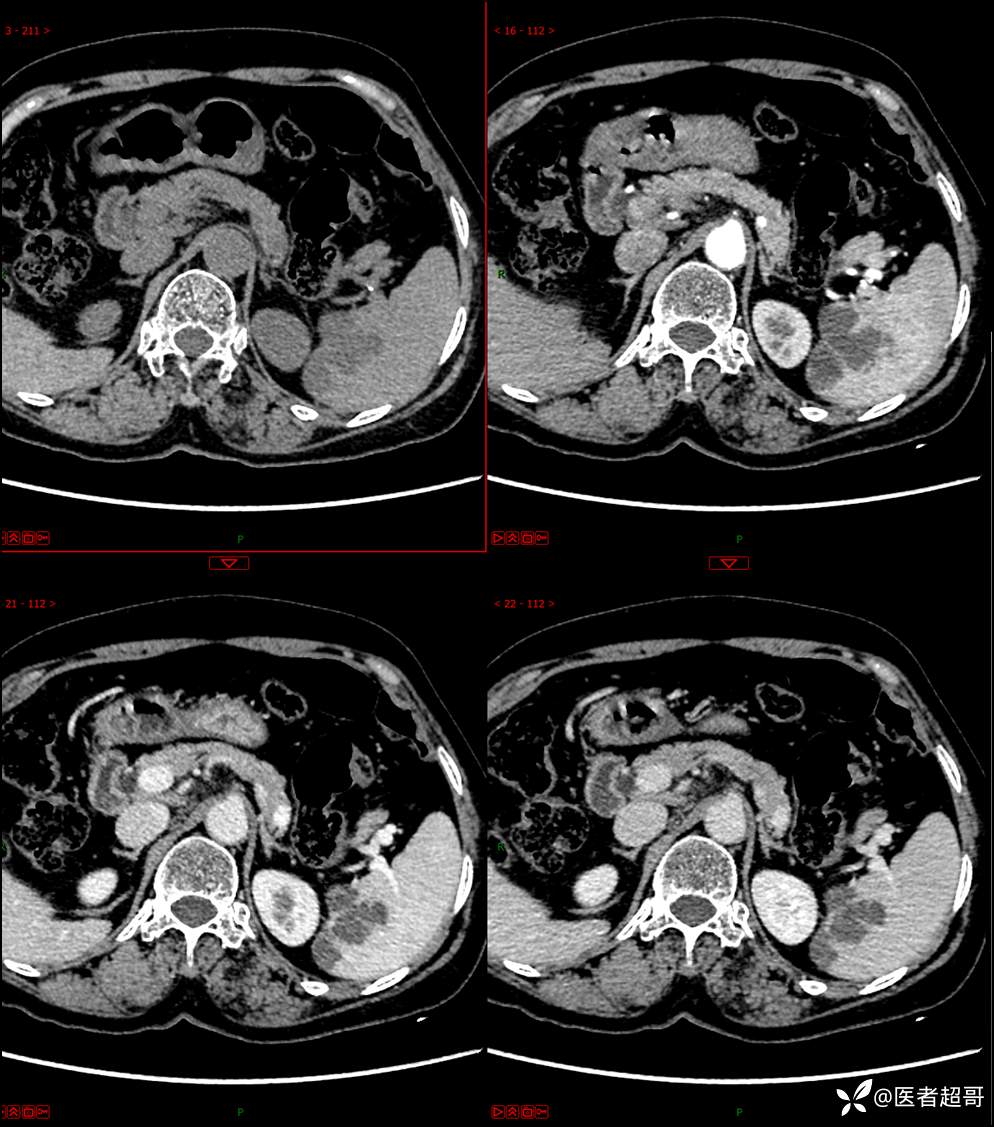

【影诊笔记598】脾脏占位03,脾脏囊性占位,回帖即可查询病理,请分析!

胡志勇HZY 达人已点赞女,64岁

主 诉:查体发现脾肿物9天。

现病史:患者9天前于市人民医院查体时发现脾脏肿物,未行处理,后于我院门诊查,上腹部CT平扫+强化:脾脏占位,考虑良性,囊肿?脉管源性病变?患者诉平素无异常不适。现患者为求进一步诊疗,门诊遂以“脾肿物”收入院。患者自患病以来,神志清,精神可,饮食、睡眠可,大小便正常,体重未见明显变化。